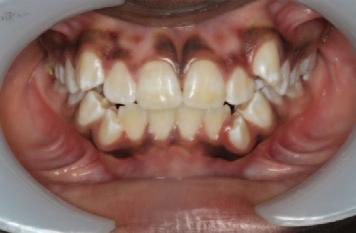

Journal of the Irish dental association by Th!nk Media - Issuu